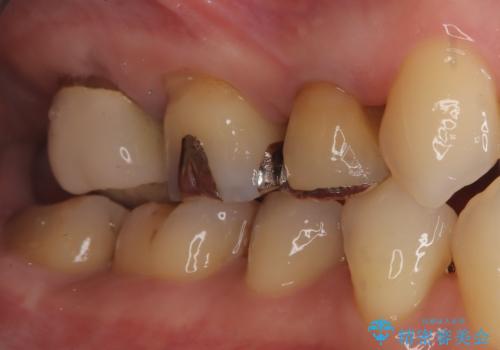

セラミッククラウンによる修復 根の状態が安定した後、5番・6番・7番の3本にセラミッククラウンを装着しました。以前のメタルインレーは歯を部分的に覆うものでしたが、今回は歯の破折リスクを抑え、全体を保護するためにフルカバーのクラウンを選択しています。

治療後は、金属特有の見た目が解消されただけでなく、精密な根管治療によって抜歯のリスクも回避されました。適合性の高いセラミックで修復したことにより、清掃性も向上し、再発しにくい清潔な口腔環境を実現しています。